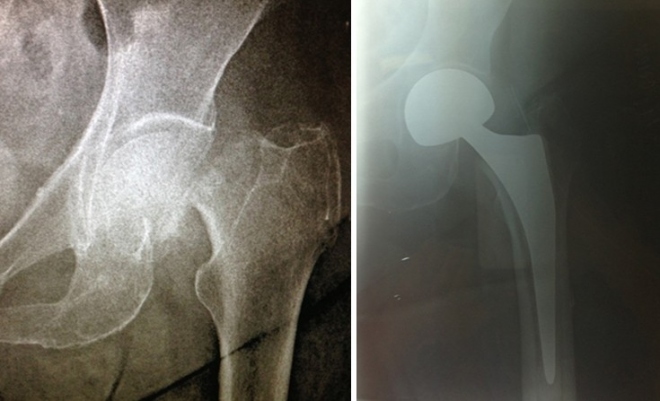

Τα υποκεφαλικά κατάγματα αντιμετωπίζονται με ημιολική ή με ολική αρθροπλαστική ισχίου. Και εδώ στόχος του χειρουργείου είναι η άμεση αποκατάσταση κι η γρήγορη κινητοποίηση του ασθενούς με τη λιγότερη απώλεια αίματος. Αυτό πετυχαίνεται με την τεχνική AMIS ισχίου.

Στην προσπέλαση του ισχίου η μοναδική MIS τεχνική είναι η AMIS (anterior minimal invasive surgery). Πέραν της τομής του δέρματος ,η AMIS είναι η τεχνική η οποία σέβεται τους μύες και τα νεύρα.

Τα πλεονεκτήματα της AMIS του ισχίου είναι:

1. Μικρή τομή του δέρματος (6-8 εκ.)

2. Μειωμένος έως μηδενικός μετεγχειρητικός πόνος.

3. Μειωμένος κίνδυνος μετεγχειρητικής χωλότητας.

4. Μειωμένη έως και μηδενική πιθανότητα μετεγχειρητικού εξαρθήματος.

5. Μειωμένη παραμονή στο νοσοκομείο.

6. Μειωμένη απώλεια αίματος.

7. Μικρότερη περίοδος αποκατάστασης.

8. Γρηγορότερη επάνοδος στις καθημερινές δραστηριότητες.